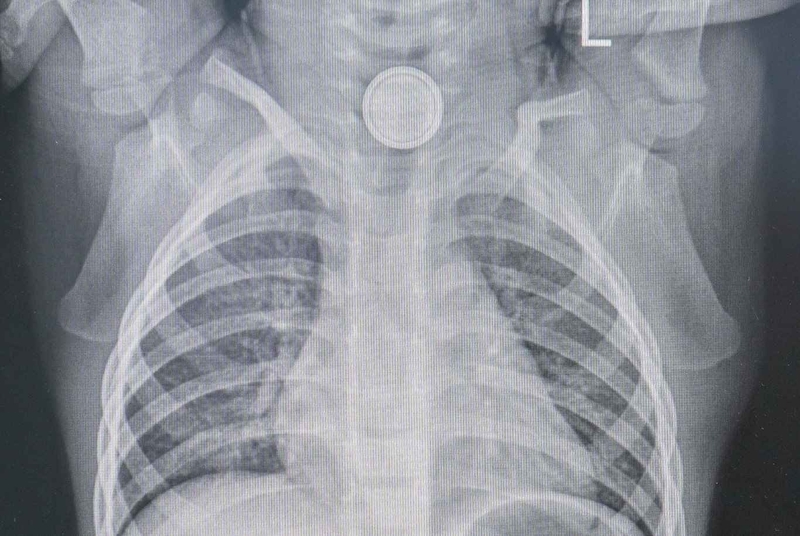

Một số vật thể lạ có thể được phát hiện bằng chụp X-quang thông thường (ưu tiên chụp 2 góc khác nhau). Tia X có thể phát hiện ra các dị vật bằng kim loại và xương rất tốt vì có đậm độ cao, ngoài ra X-quang cũng có thể giúp phát hiện các dấu hiệu thủng (ví dụ, khí tự do trong trung thất hoặc phúc mạc).

Triệu chứng và cách xử trí dị vật đường ăn 2

Dị vật đồng xu

Tuy nhiên, xương cá và thậm chí một số xương gà, gỗ, nhựa, thủy tinh và các vật kim loại mỏng có thể khó xác định trên phim X-quang thông thường. Nếu có bất kỳ nghi ngờ nào về dị vật hoặc cố ý hoặc nguy hiểm, nuốt phải dị vật, có thể chỉ định chụp CT, hoặc nội soi để xác nhận và định vị dị vật. Nội soi qua đường thực quản thường được chỉ định ở những bệnh nhân nghi ngờ nuốt phải dị vật và có các triệu chứng tiếp diễn mặc dù kết quả hình ảnh âm tính.